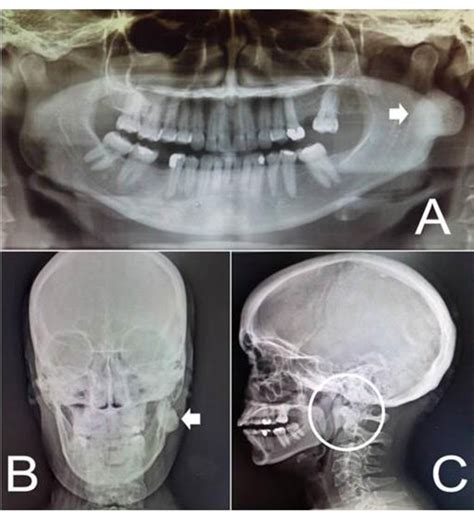

Caso 638, varón, 29 años Mucocele en el seno maxilar izquierdo y osteoma en el complejo etmoidal del lado izquierdo En la visita a nuestra clínica el paciente refirió un dolor en la zona del seno maxilar izquierdo. En la radiografía panorámica practicada se observó un seno maxilar izquierdo completamente velado y un engrosamiento de la mucosa basal en el seno maxilar derecho (fig. 1). Se identificaron además diversos dientes que requerían tratamiento odontológico.

Debido al gran malestar del paciente, se realizó una tomografía volumétrica digital dental (TVD) para el estudio diagnóstico de los demás senos paranasales.

En la TVD se observa un seno maxilar izquierdo íntegro y homogéneamente ocupado, además de una obstrucción del ostium fisiológico en ambos lados. Se aprecia también una opacificación subtotal de todo el complejo etmoidal y también del seno frontal. Estos hallazgos sugieren un diagnóstico de mucocele del seno maxilar izquierdo y de pansinusitis de los senos paranasales.

En el lado izquierdo, en la zona de las celdas etmoidales superiores se observa una masa circunscrita de densidad similar a los tejidos duros junto con una obstrucción parcial de las celdas etomoidales izquierdas. Se trata probablemente de un osteoma.